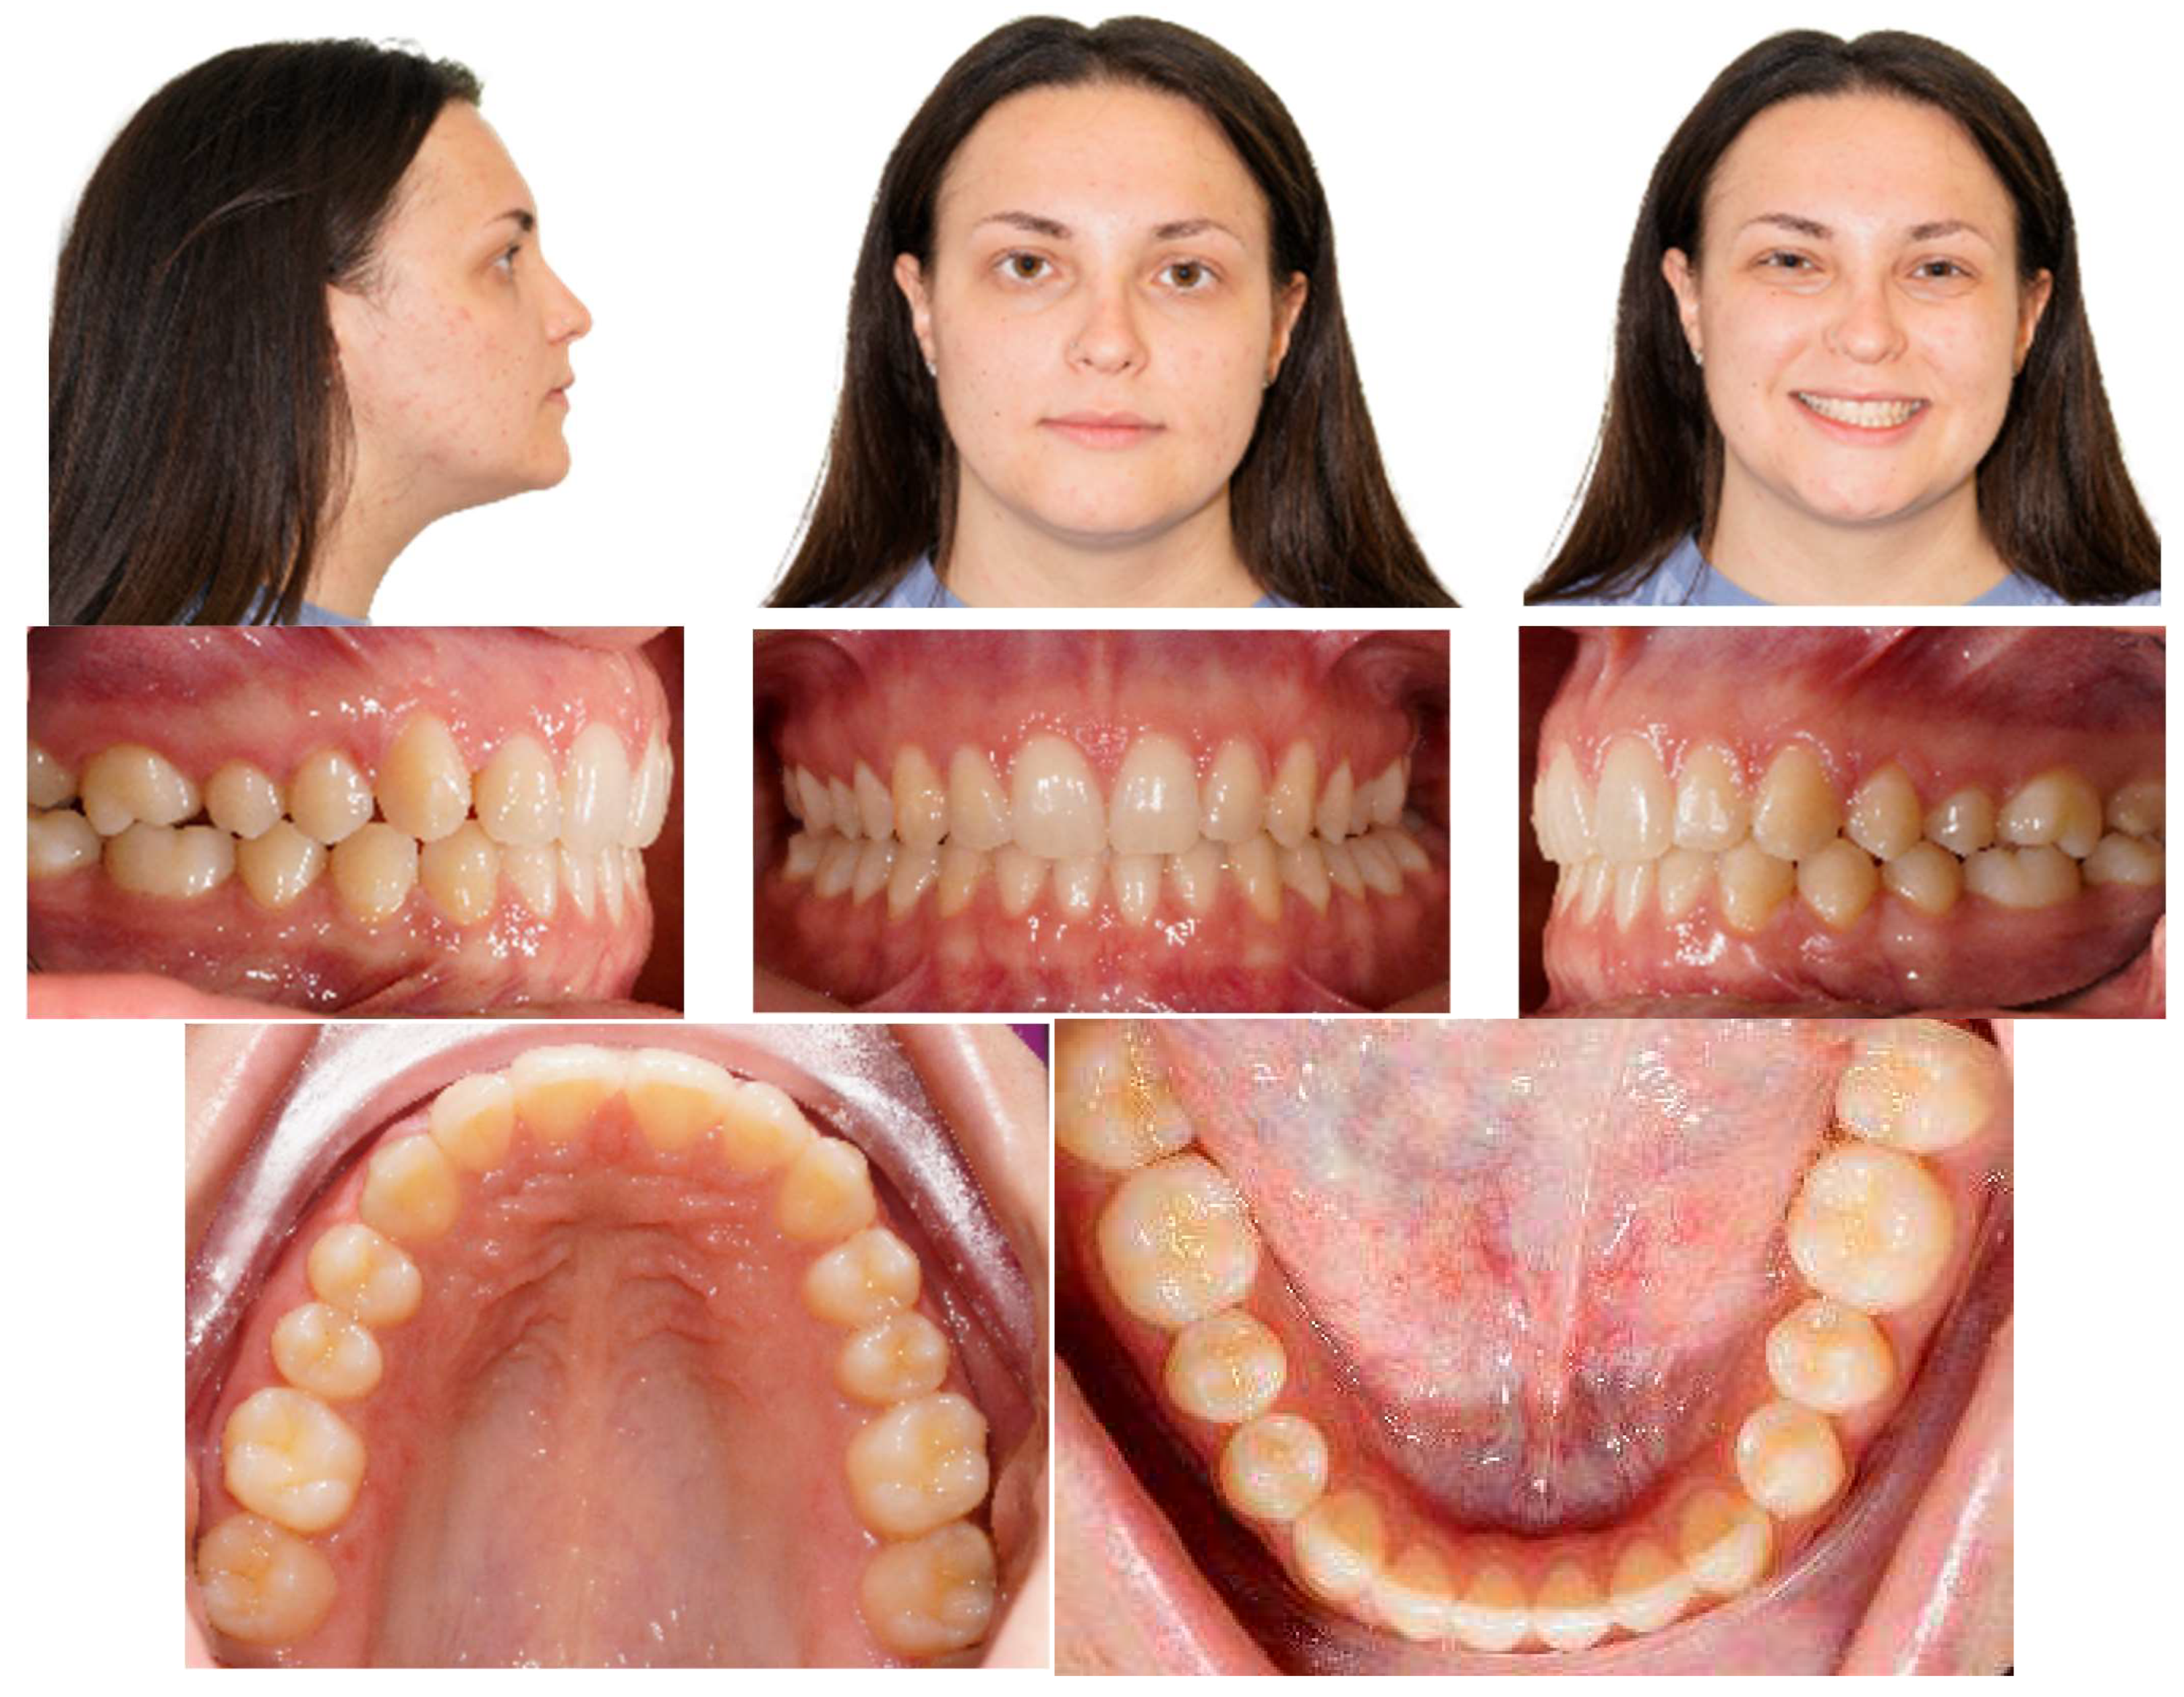

Post-treatment records of the patient successfully treated using a combination of cantilever mechanics with TADs and clear aligners show a control of the facial aesthetics from the frontal and lateral perspectives with a harmonious soft-tissue profile. Final clinical records show good aesthetics and the functional recovery of the upper canines in the arch. A Class I canine relationship was achieved, and overbite and overjet were normalized. The correction of crowding was carried out (Figure 17).

Figure 17.

Post-treatment extraoral and intraoral pictures.

At the end of the treatment, cephalometric radiographs show the good control of the upper and lower inclination. The radiographic evaluation shows an ideal root parallelism and a preserved periodontal health in the canine region (Figure 18). Retention was achieved through Vivera in the upper arch and via a bonded lingual retainer in the lower arch. No TAD failures were observed.